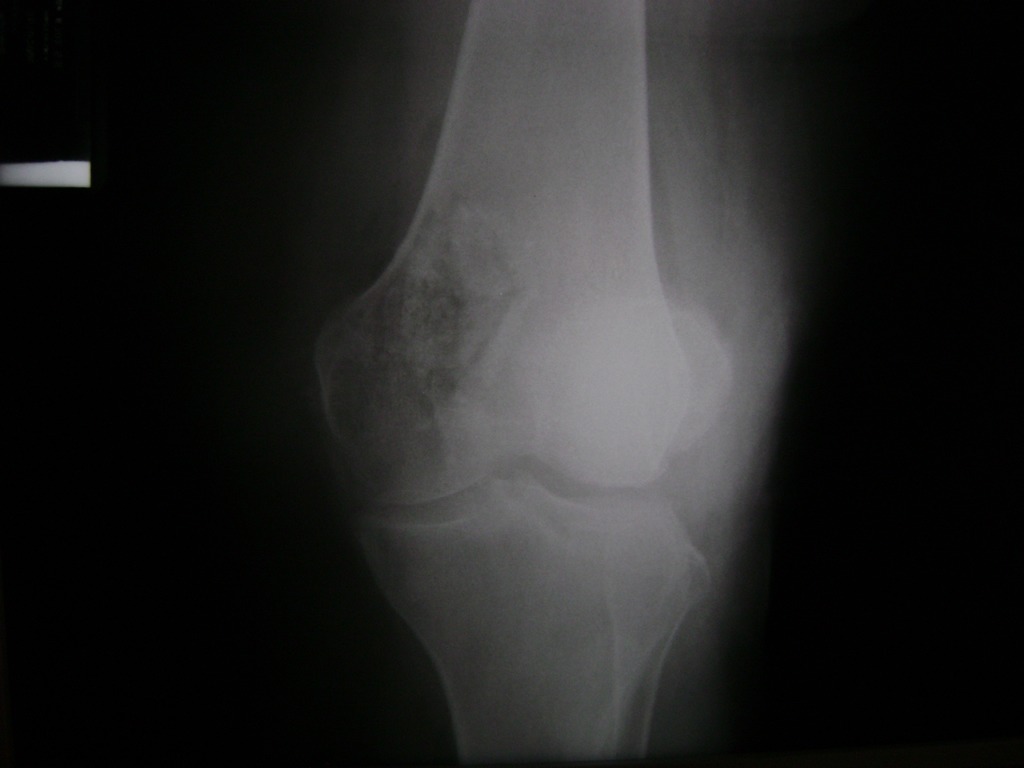

Cirugía de Fémur - Rodilla